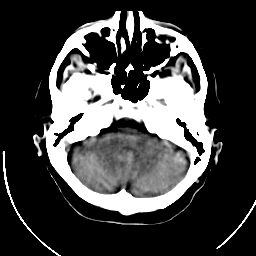

2. CT(计算机断层扫描)

原理:

- X射线管旋转发射扇形束(64排以上为锥形束)

- 探测器阵列接收衰减后的X射线

- 通过滤波反投影算法重建断层图像

- 亨氏单位(HU)量化组织密度(水=0,骨>400)

技术演进:

- 单层→多层螺旋CT(现多为128-640层)

- 能谱CT(双能量物质分离)

- 低剂量CT(肺筛查剂量<1mSv)

优势:

- 扫描速度快(胸腹联合扫描<10秒)

- 骨结构显示清晰(骨折、钙化)

- 急诊首选(卒中、创伤)

局限:

- 辐射剂量较高(胸CT约7mSv)

- 软组织对比度差

临床应用:

- 急性出血(脑出血、内脏破裂)

- 肺部小结节筛查

- 冠脉钙化评分